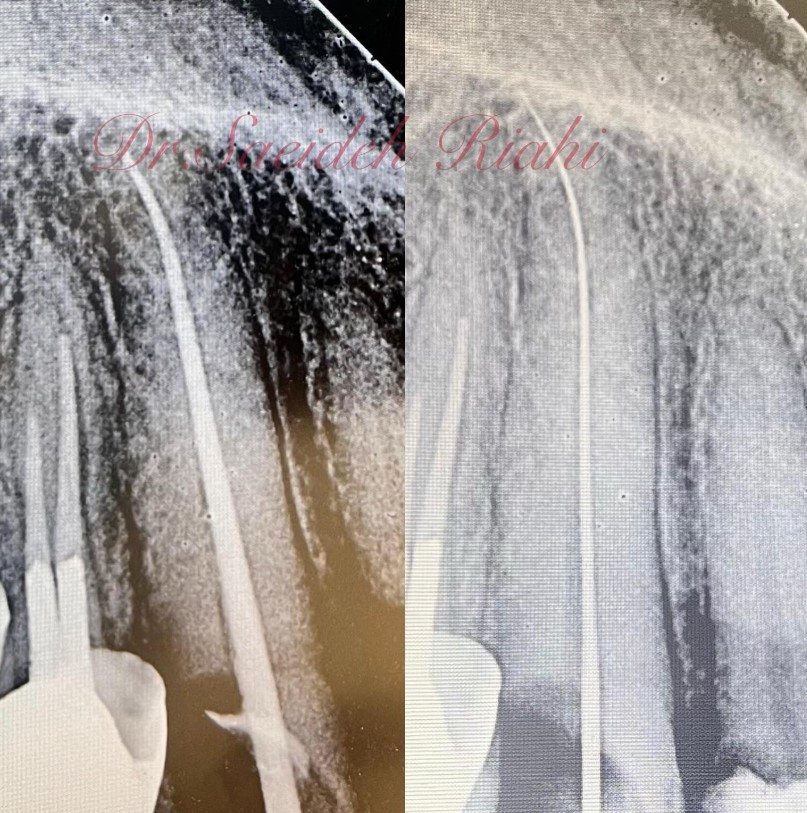

در این درمان، عصب (پالپ) آسیب‌دیده از داخل کانال دندان برداشته شده، سپس فضای داخلی کانال‌ها تمیز، ضدعفونی و با مواد مخصوص پر می‌شود تا از گسترش عفونت و درد جلوگیری شود.

عصب کشی دندان